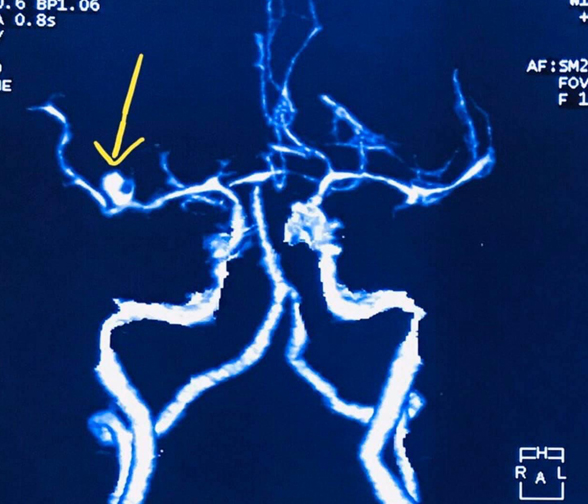

- Clip ligation of brain aneurysms (open microsurgery)

CT scan and/or MRI films or CDs must be brought including pertinent laboratory results/ medical records in order for us to provide you with a sound neurosurgical assessment.